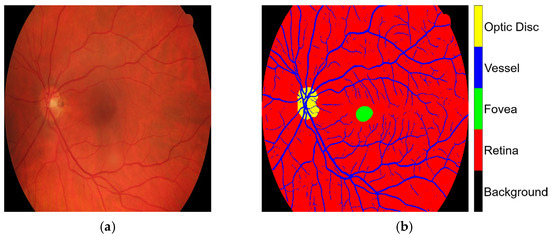

The following procedure is outlined in Figure 2. The modified datasets, DRIVE and CHASE-DB1, underwent preprocessing to adjust the spatial resolution to 1024 × 1024 pixels through the application of nearest neighborhood interpolation on both the images and their corresponding masks. These datasets provided the training data for the CJA-RN50DLv3+ model, which was instrumental in initializing the segmentation of major anatomic structures of the retina. The obtained HRF training dataset was randomly partitioned into three subsets, with sub_HRF-1 and sub_HRF-2 each comprising ten images, while sub_HRF-3 comprised the remaining images. The subset sub_HRF-1 was utilized for the fine-tuning of the CJA-RN50DLv3+ model. The fine-tuned model was evaluated on sub_HRF-2 to determine its efficacy in accurately segmenting retinal structures. Some evaluative results are illustrated in Figure 4. These submodules facilitated the preparation of the model for the CJA process.

Figure 1. Example from the HRF dataset: (a) original retinal image, Image1024-02_g; and (b) corresponding ground truth annotation.